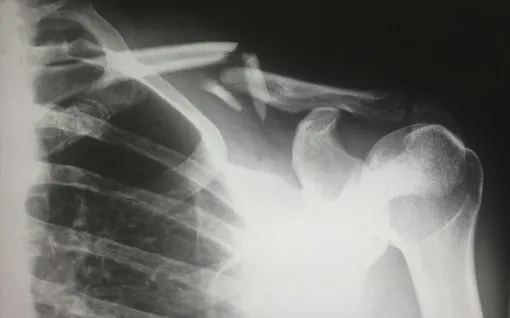

В последнее время в социальных сетях стали распространяться данные масштабного исследования с участием 150 тысяч пациентов, согласно которым прием «Оземпика» якобы на 30 процентов повышает риск развития остеопороза и остеомаляции.

Врач-эндокринолог Анна Одерий объяснила, что проведенное исследование имеет исключительно наблюдательный характер: оно фиксирует совместное возникновение явлений, но не доказывает причинно-следственную связь. Пациенты, принимающие агонисты GLP-1, обычно относятся к старшей возрастной группе, страдают ожирением и диабетом, а также пьют другие лекарства.

«Каждый из этих факторов сам по себе повышает вероятность болезней опорно-двигательного аппарата», — отметила специалист.

Одерий также обратила внимание на разницу между относительным и абсолютным риском, которому в доказательной медицине отдается приоритет. Рост риска на 30 процентов в абсолютных значениях означает разницу всего в три случая на тысячу человек, когда заболевание выявляют у 13 принимающих препарат пациентов против 10 человек без лечения.

Некоторые исследования и вовсе фиксируют нейтральный или слегка положительный эффект на кости благодаря улучшению метаболического контроля.

По словам врача, небольшое снижение минеральной плотности костей действительно может происходить, но это связано с самим фактом быстрого похудения. Любое резкое снижение массы тела уменьшает механическую нагрузку на скелет.

«При выраженном дефиците веса, нехватке кальция и витамина D, а также на фоне гормональных изменений возрастает риск изменения процессов ремоделирования костной ткани», — добавила Татьяна Губина.